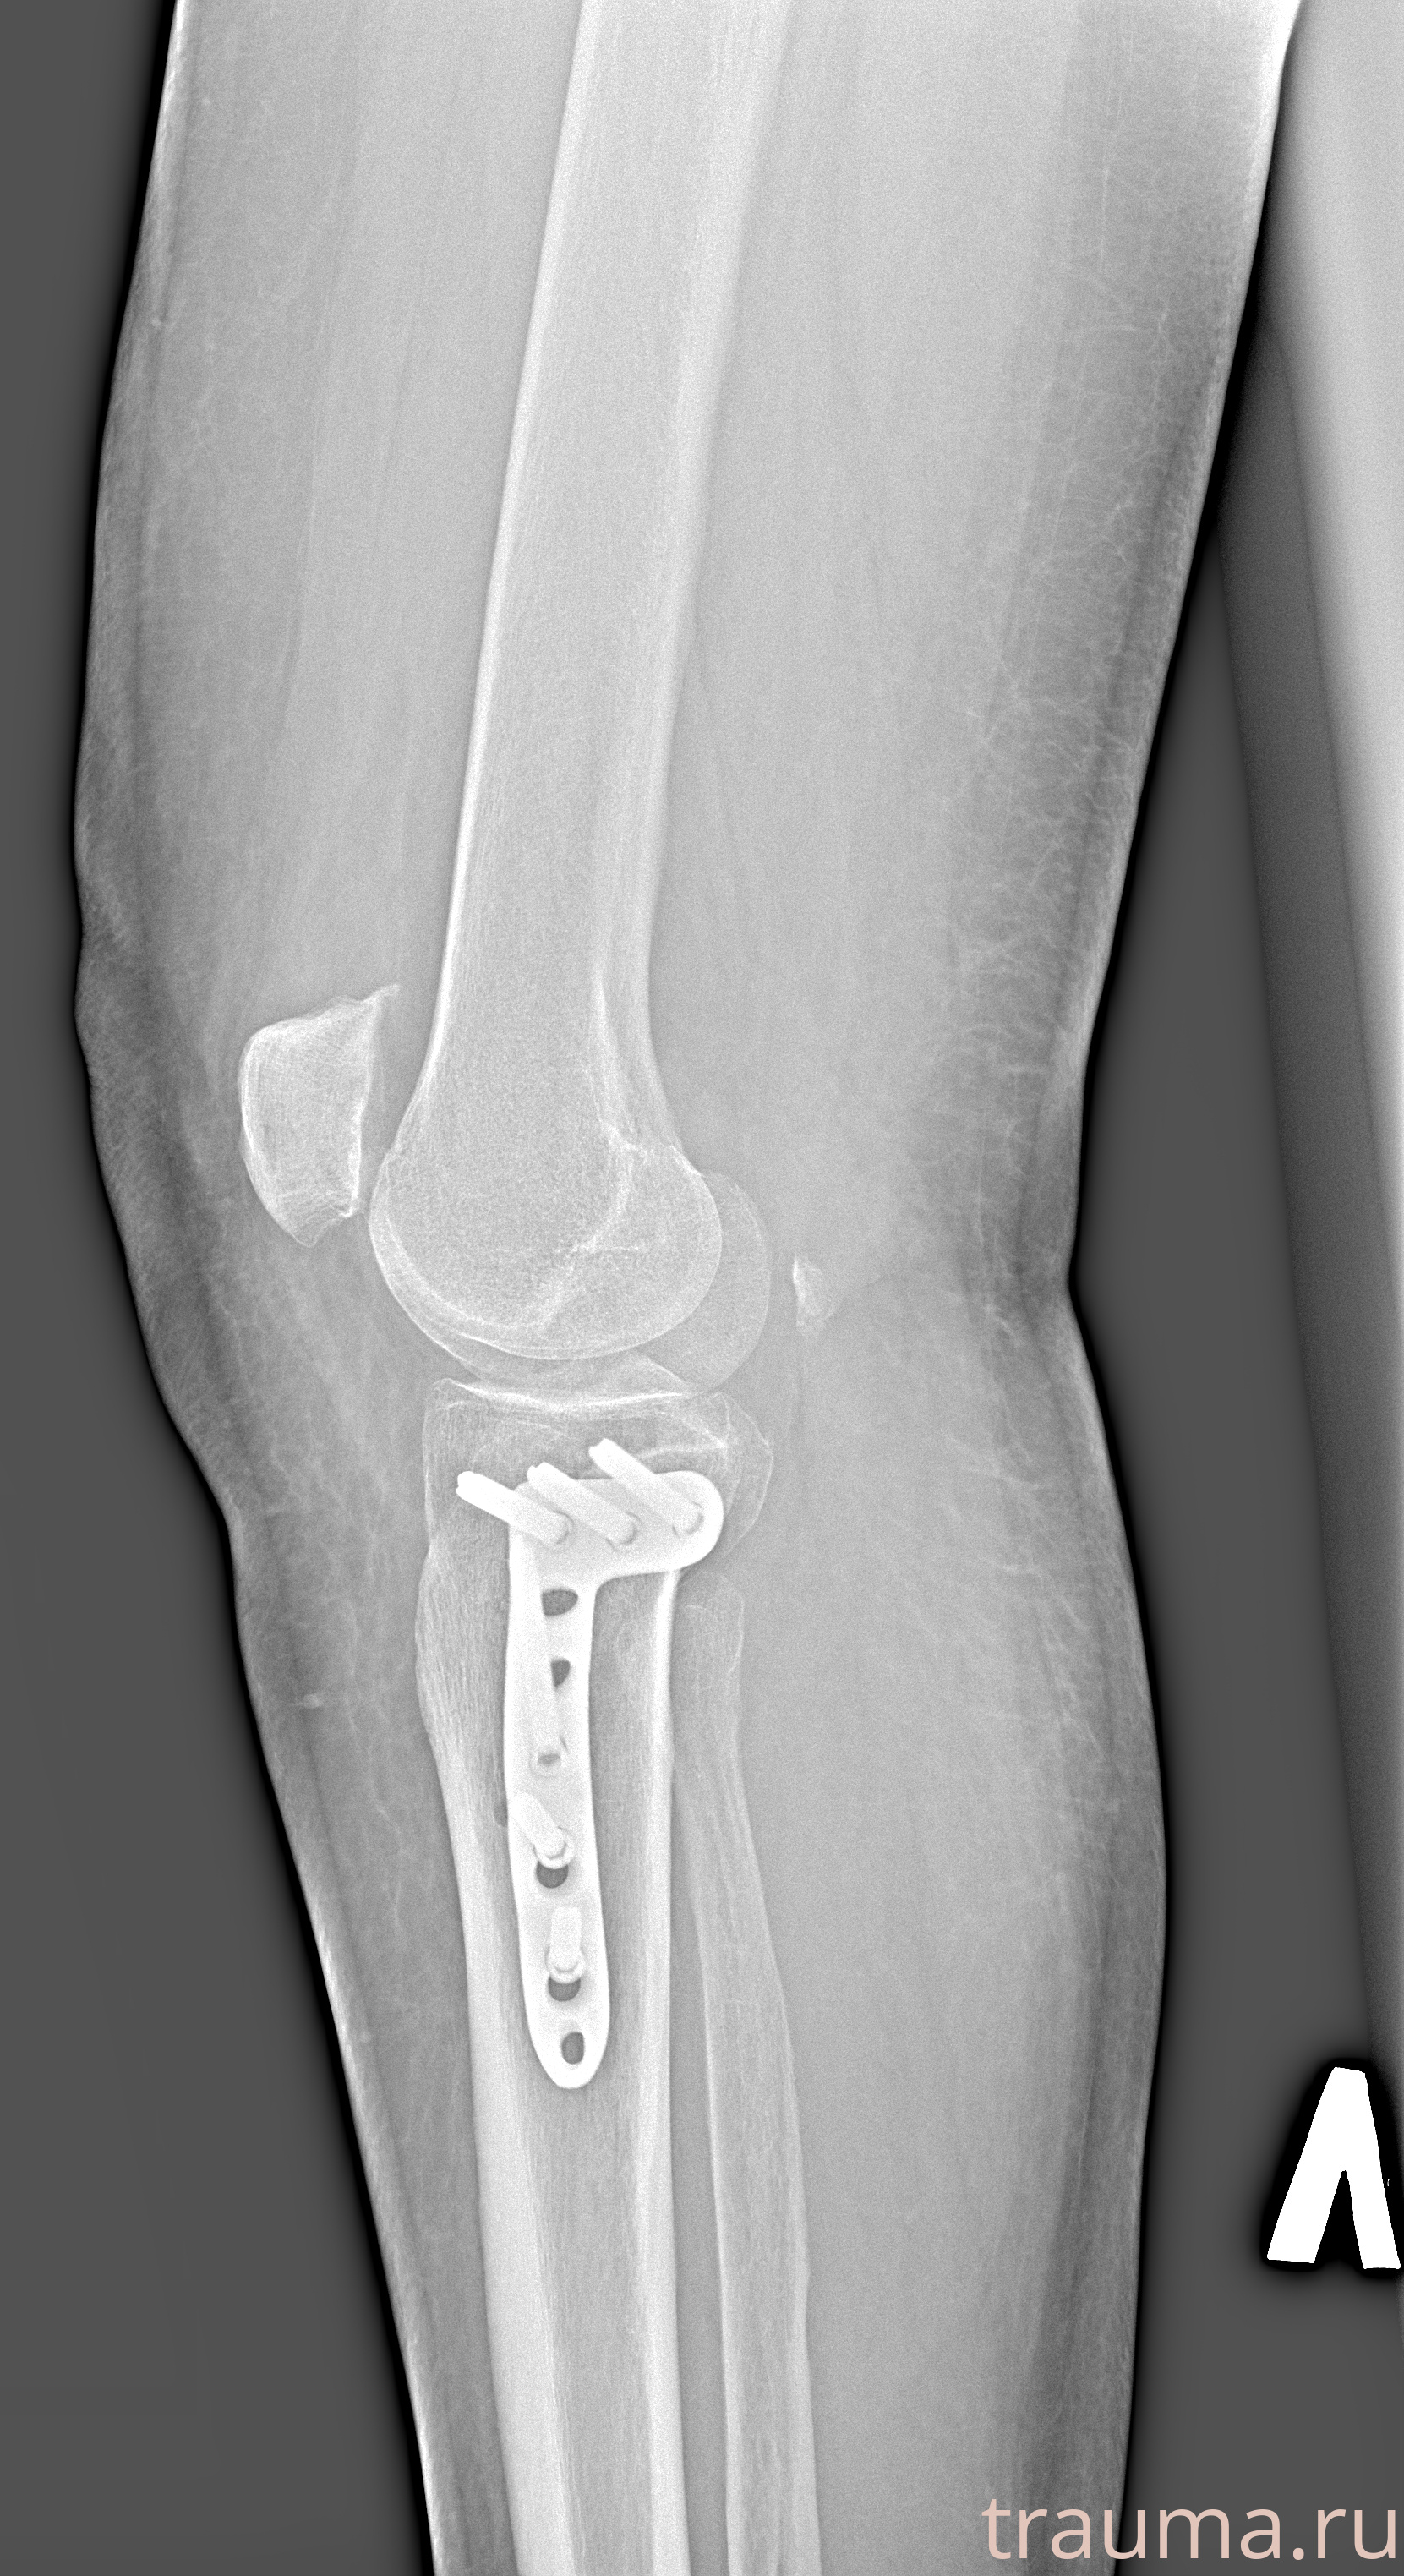

Рентгенограммы